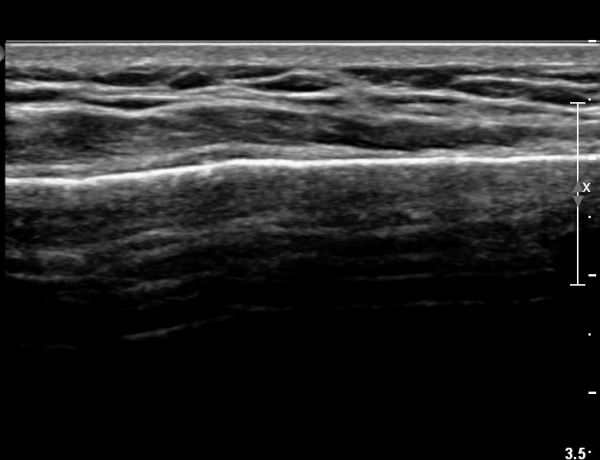

Á¶±Ý ´õ ¸»´ÜÀ¸·Î À̵¿ÇÏ´Ï Äá¾Ë»À ÇÇÁú°ñ ¿¬¼Ó¼º ¼Ò½ÇÀÌ °üÂûµÊ(»çÁö 3),

Äá¾Ë»À Á¾´Ü¸é°Ë»ç¿¡¼­ Äá¾Ë »À ±ÙÀ§ºÎÀÇ ÇÇÁú°ñ °ß¿­ÀÌ °üÂûµÊ(»çÁö 4).